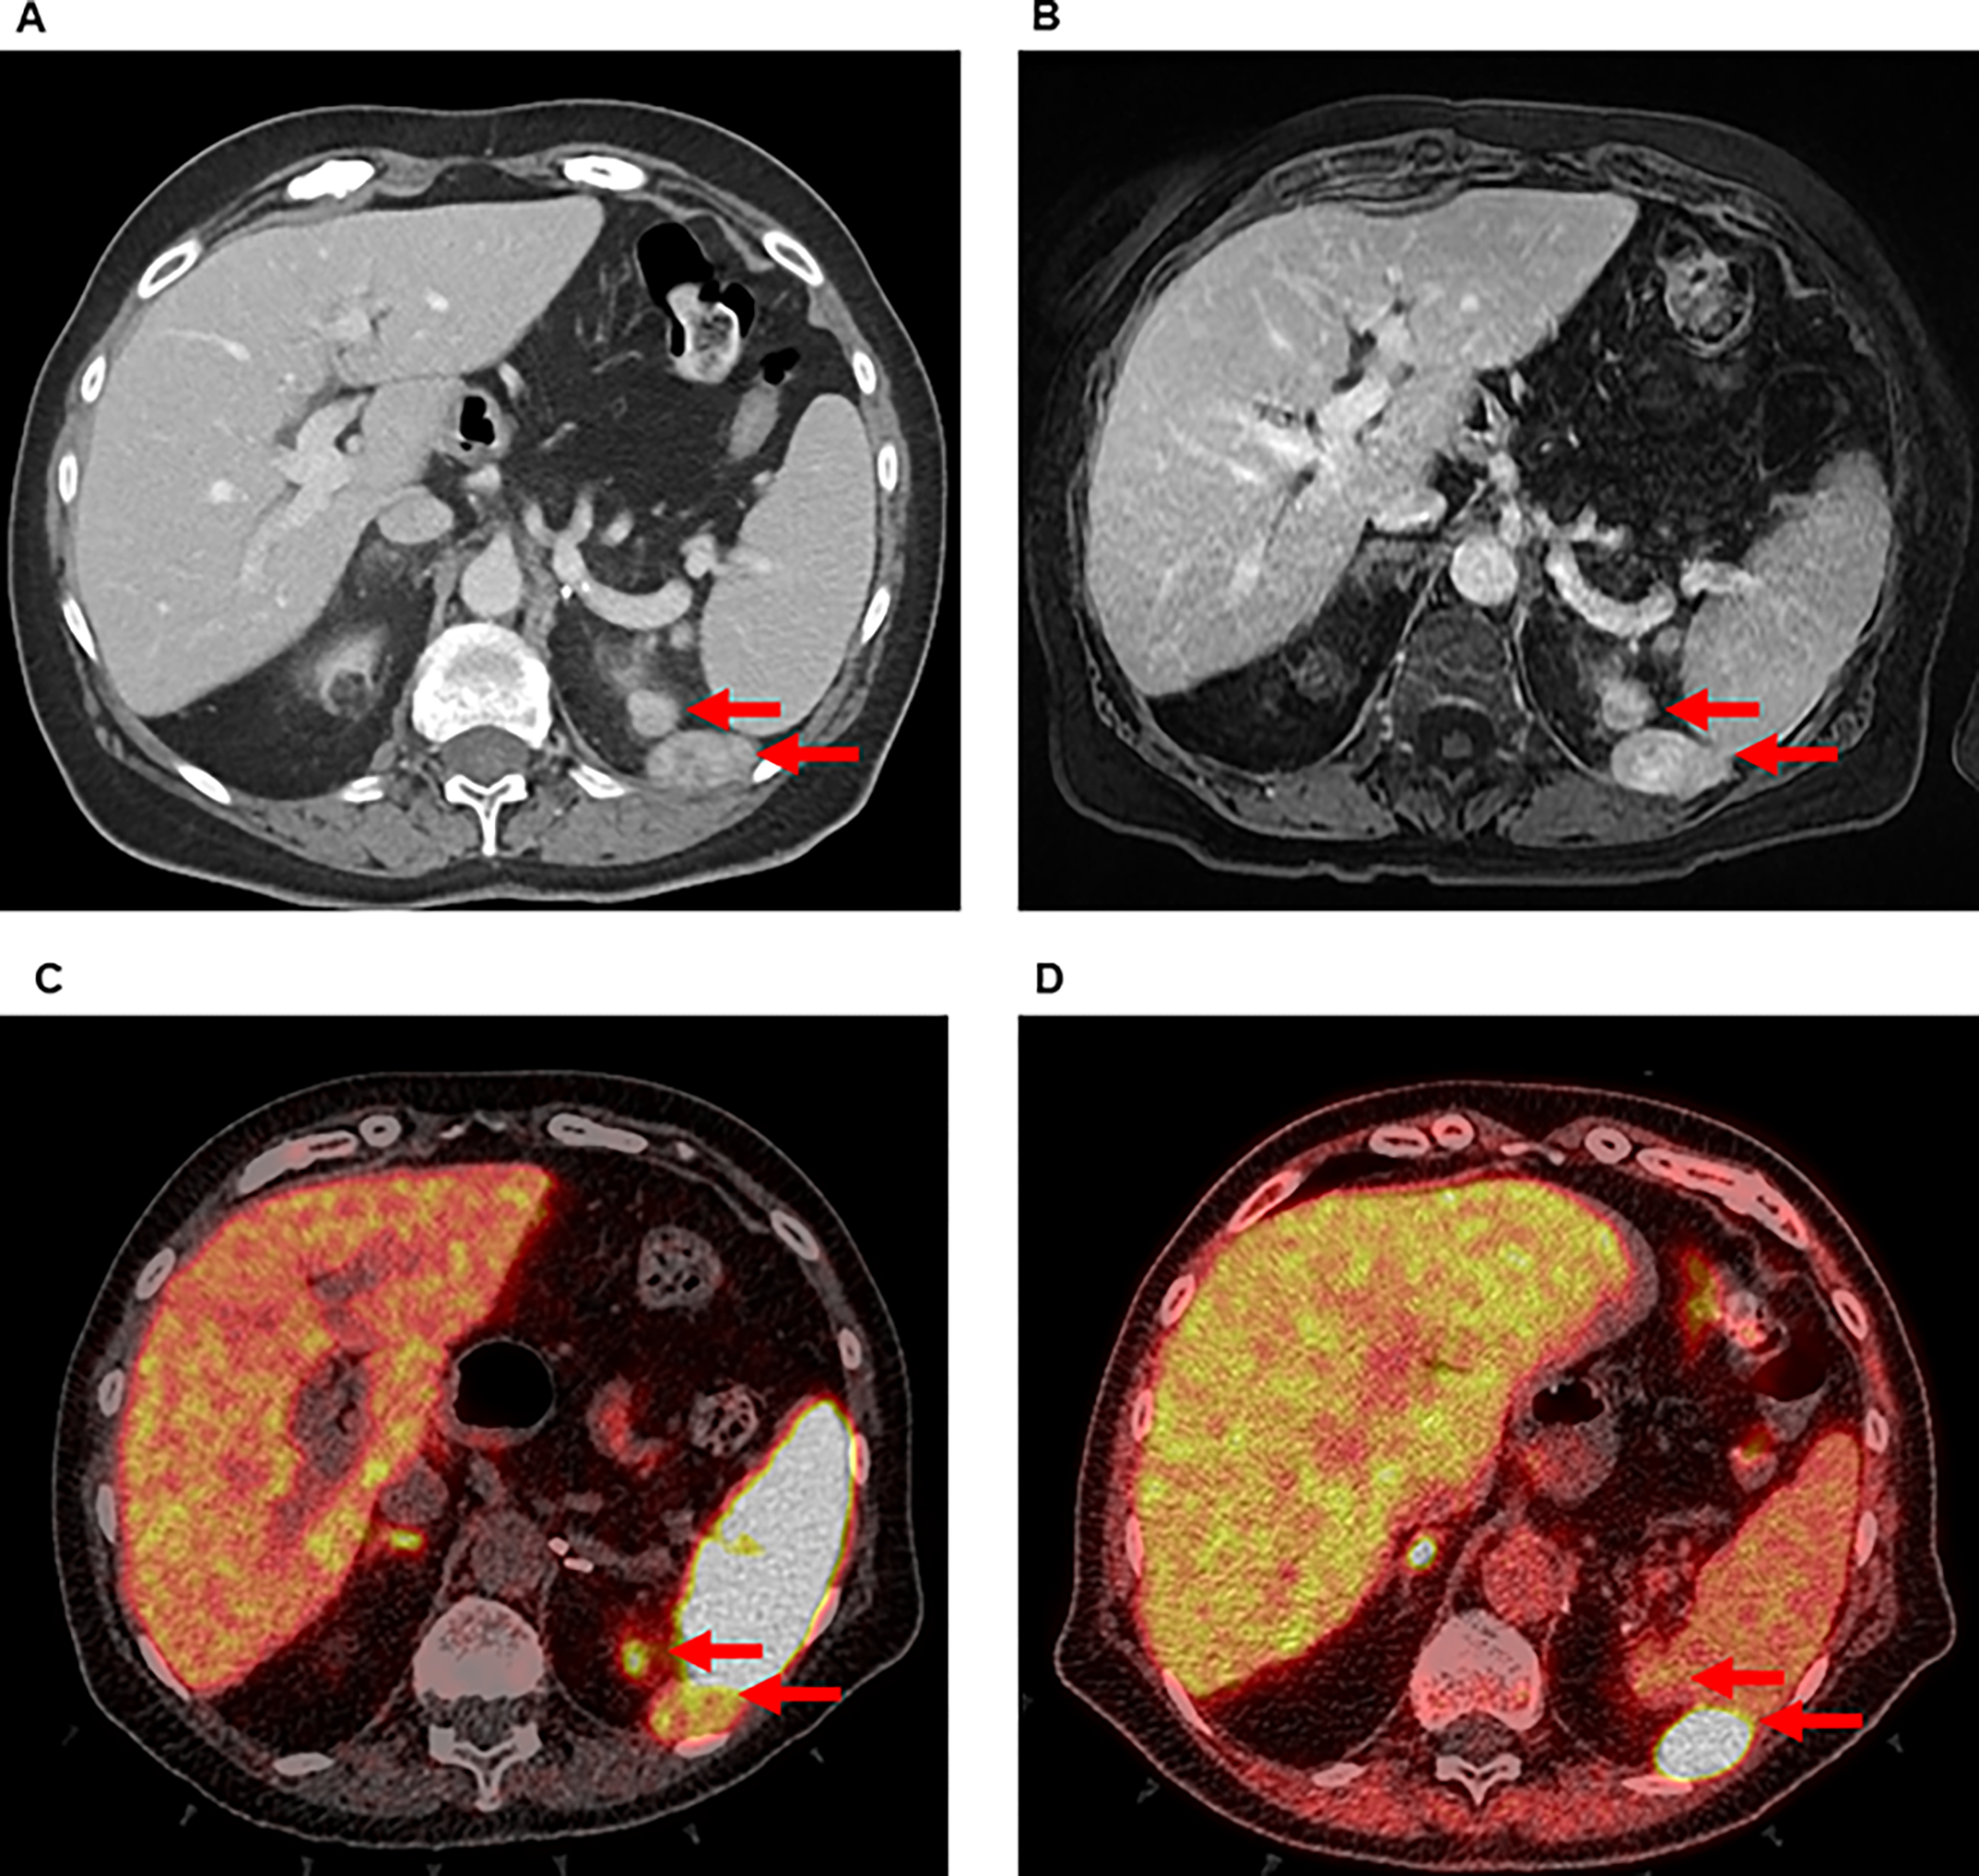

A 72-year-old female presented to the NIH Warren Magnuson Clinical Center after the discovery of recurrent PCC. There was no family history of PCC or other phenotypes of PCC-related syndromes. She had previously undergone a laparoscopic transperitoneal left adrenalectomy at an outside institution over ten years before being evaluated at NIH. The pathology report from this initial operation noted a 2.5 cm PCC with extensive laceration, indicating tumor rupture during surgery. She did not have subsequent surveillance. One year before establishing care at the NIH, she had a hypertensive ischemic stroke, leaving her with persistent slurred speech secondary to right-sided cranial nerve XII palsy. Workup led to the discovery of recurrent PCC. The hypertensive episodes secondary to her recurrent PCC were managed with doxazosin and propranolol. Preoperative workup demonstrated elevated plasma metanephrine of 390 pg/mL (reference range 12–61 pg/mL), normetanephrine of 742 pg/mL (reference range 18–112 pg/mL), epinephrine of 125 pg/mL (reference range 0–50 pg/mL), and norepinephrine of 2904 pg/mL (reference range 112 – 750 pg/mL) – levels consistent with PCC. Twenty-four-hour urine studies demonstrated markedly elevated normetanephrine of 3210 mcg/24 hours (reference range <900 mcg/24 hours) and metanephrine of 2330 mcg/24 hours (reference range <400 pg/mL). Genetic testing did not demonstrate any pathogenic germline mutations in genes known to cause hereditary PCC syndromes. A contrast-enhanced CT scan and a gadolinium-enhanced MRI of the abdomen showed numerous hypervascular lesions near the left diaphragm, kidney, paracolic gutter, and spleen (Figure 1a and b). 68-Gallium DOTATATE PET/CT and 18-FDOPA PET/CT revealed radioavid tumors, consistent with recurrent PCC in the left adrenal bed (Figure 1c and d). The consensus reached at a multidisciplinary tumor board was to offer a surgical resection to control her hypertension and to reduce the risk of catastrophic cerebrovascular or cardiovascular events. She was admitted preoperatively for blood pressure control via alpha adrenoceptor blockade with phenoxybenzamine.

Figure 1:

Preoperative imaging of a patient with recurrent PCC in left upper quadrant of the abdomen by (A) CT, (B) MRI, (C) 68-Ga DOTATATE PET/CT, and (D) 18-FDOPA PET/CT. Arrows indicate radiographically detectable lesions.